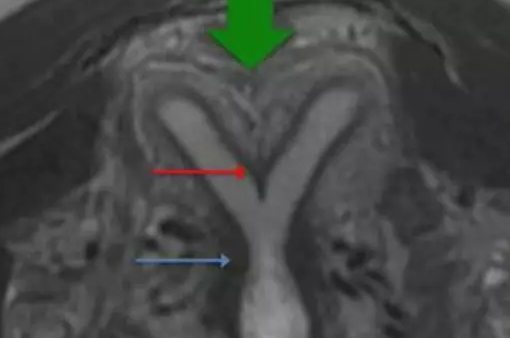

縱隔子宮、雙角子宮都是雙側副中腎管融合不良所致的畸形,在聲像上有很多相似之處,尤其是不完全縱隔子宮與雙角子宮較難鑒別,兩者主要是從子宮外形上予以區別。

雙角子宮是雙側副中腎管尾部已經融合,末端中隔已被吸收,子宮底部融合不良,宮底較寬,兩宮角有一較深外形似羊角的凹陷,兩側各具一宮腔,雙側卵巢多正常。

縱隔子宮是雙側副中腎管已完全融合,其中隔未吸收或未完全吸收,形成程度不同的縱隔,但子宮外形正常。縱隔將宮腔一分為二,其中縱隔完全存在者稱之為完全性縱隔子宮,縱隔已部分消失的稱之為不完全性縱隔子宮。